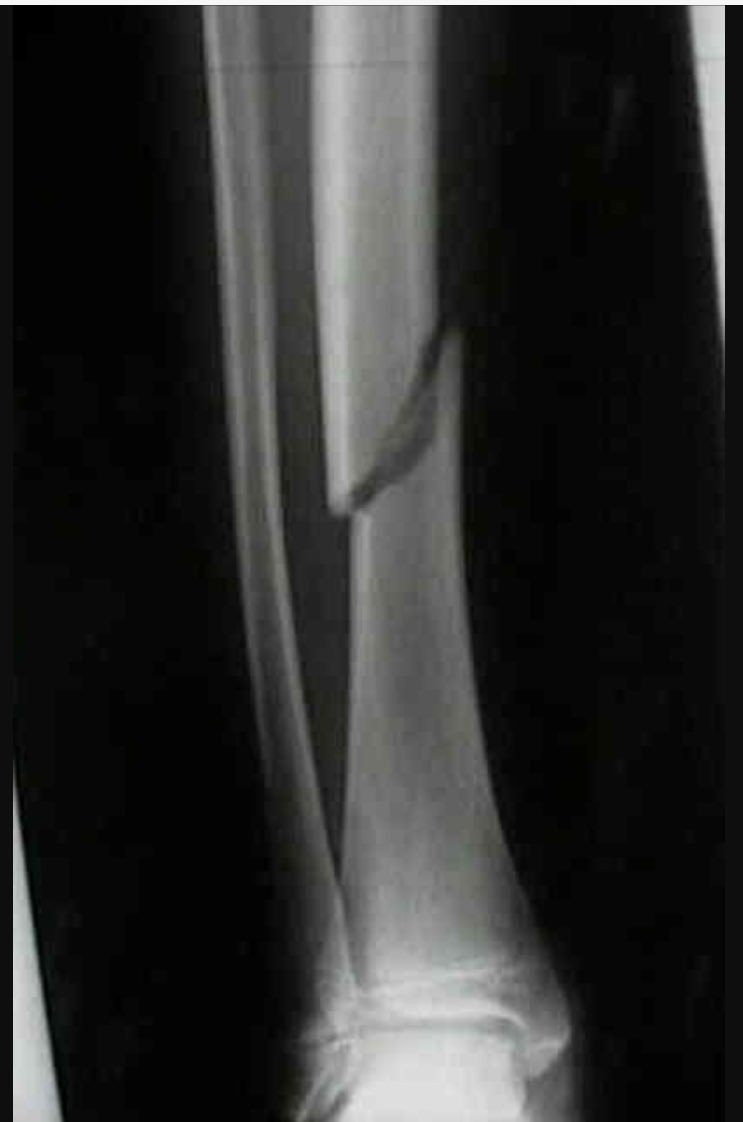

What type of fracture is this, what bone is it and what view is this?

Oblique fracture

Tibia

AP